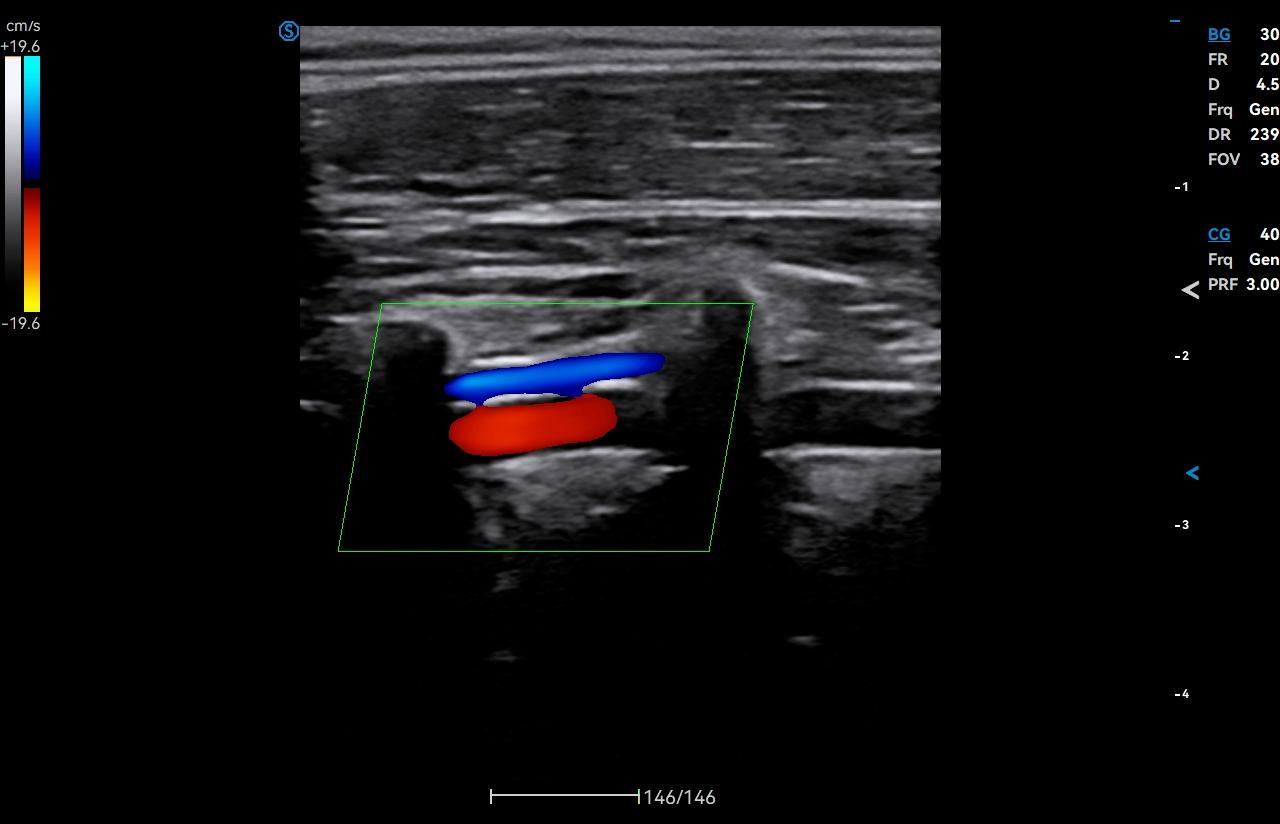

- Category: Color Doppler

Click on images to enlarge

Click on images to enlarge

VS Flow is highly sensitive to low velocity blood flow signal and especially suitable for superficial blood flow examination